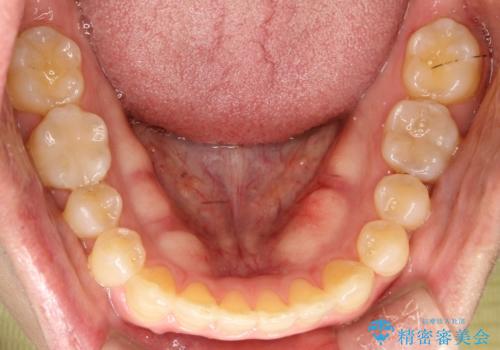

前歯の隙間 インビザラインにて整った歯並びへ

- 前歯の隙間が気になるとのことで来院されました。

インビザラインにて矯正治療を行うこととしました。

下の歯と歯の間にわずかに隙間をつくり、上の前歯の隙間を閉じました。